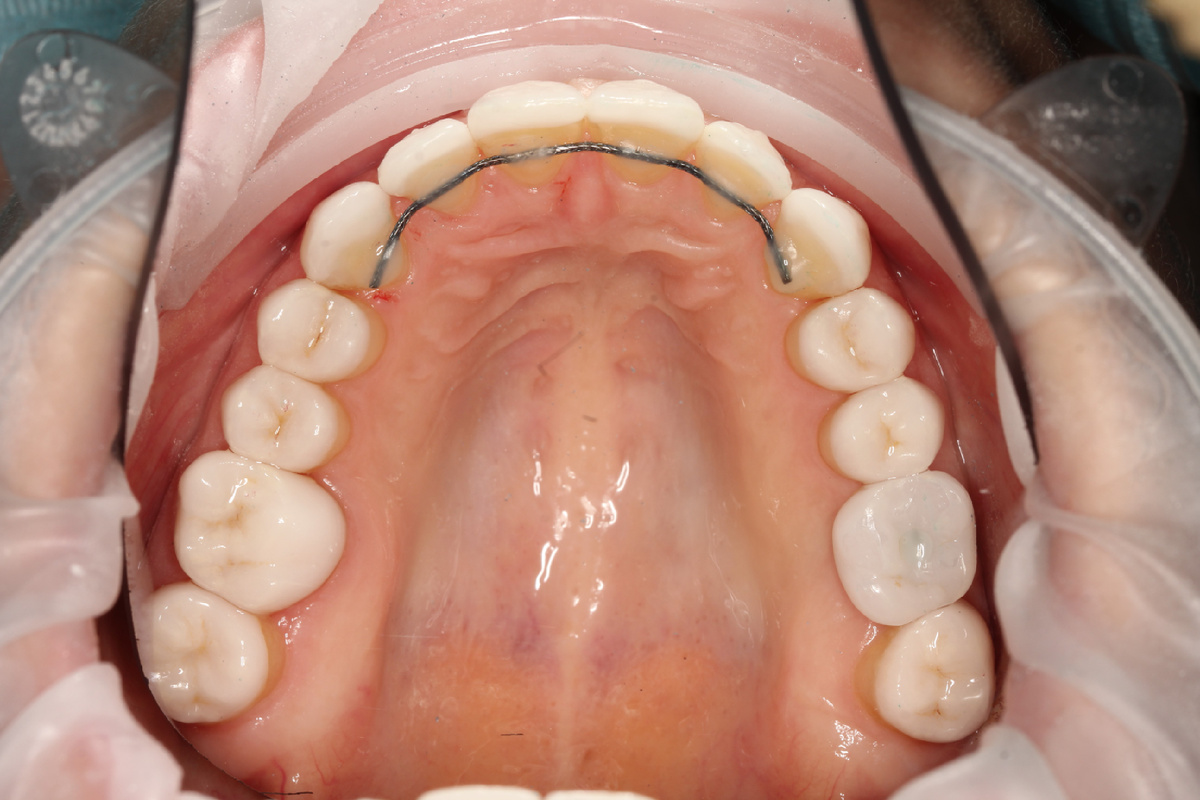

1. Отсутствие или не соблюдение правил ретенционного периода. Этот этап представляет собой фиксацию и стабилизацию достигнутого лечения. Для закрепления положения зубов в прикусе используют ретейнеры на верхнюю и нижнюю челюсть. Они бывают съемные и несъемные. Несъемные ретейнеры представляют собой проволоку, установленную на внутренней поверхности зубов на верхней и нижней челюсти. Съемные ретейнеры или ретенционные капы — это пластиковые капы, которые пациент должен носить каждую ночь.

В данном кейсе пациенту не устанавливались ретейнеры, что и стало причиной повторного обращения к стоматологу-ортодонту, но уже в нашу клинику.

Зарина Касымкановна провела восстановительную работу на элайнерах длительностью 2 года. За этот период дополнительно применялись эластики — ортодонтические резинки. Эластичные тяги играют важную роль в исправлении смыкания: они создают дополнительные силы, способствующие более эффективному перемещению зубов и исправлению положения челюстей. Таким образом была скорректирована: